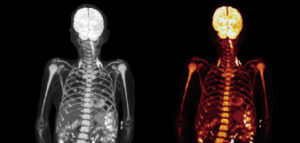

TB-PET can be used to capture molecular processes from all organs simultaneously. The high-performance instrument can be used to study diseases that affect the entire body and build a better picture of complex processes such as ageing, metabolism, brain signalling and drug interactions.

Due to its exquisite sensitivity, it also has the potential to use much lower radiation doses compared to conventional PET scanners, making it safe to scan children, healthy volunteers, and to scan patients repeatedly to better understand disease progression and treatment effects.

Overview of the technical specifications and capabilities of the new Biograph Vision Quadra Total Body PET system set to be installed.